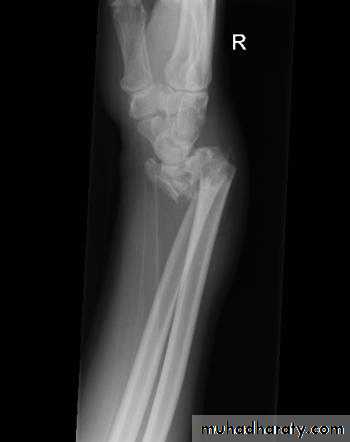

Upper limb

Fall on out stretched hand

xray

40 years male fall on out streched hand

Radial nerve palsy after reduction